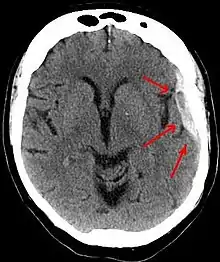

| Subdural hematoma as marked by the arrow with significant midline shift | |

On a CT scan, subdural hematomas are classically crescent-shaped, with a concave surface away from the skull. However, they can have a convex appearance, especially in the early stages of bleeding. This may cause difficulty in distinguishing between subdural and epidural hemorrhages. A more reliable indicator of subdural hemorrhage is its involvement of a larger portion of the cerebral hemisphere. Subdural blood can also be seen as a layering density along the tentorium cerebelli. This can be a chronic, stable process, since the feeding system is low-pressure. In such cases, subtle signs of bleeding—such as effacement of sulci or medial displacement of the junction between gray matter and white matter—may be apparent.